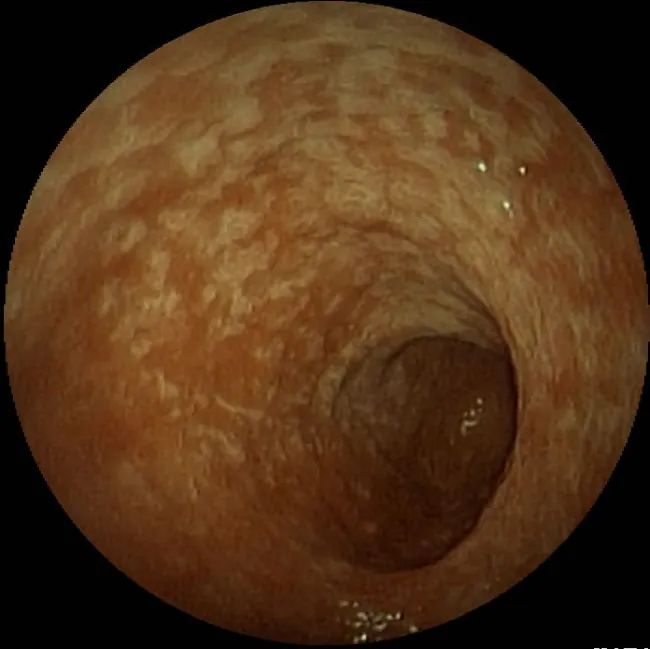

Acute gastritis is usually caused by an irritant, such as aspirin or NSAID use, heavy alcohol use, smoking, and certain infections. It can also be stress induced, caused by a decrease in bicarbonate concentration in the mucosal lining of the stomach. Chronic gastritis most commonly is caused by Helicobacter pylori infection (Figure 19.12) but can also be caused by autoimmune disease, Crohn’s disease, gastric surgery, and other infections, such as HIV. There is an increased risk for complications, including gastric cancer, peptic ulcers, and gastric bleeding or perforation, when gastritis is untreated (Azer et al., 2023).

Chronic gastritis caused by H pylori infection.

Figure 19.12 This image shows chronic gastritis caused by H. pylori infection. (credit: “Helicobacter gastritis 2.jpg” by Med_Chaos/Wikimedia Commons, Public Domain)